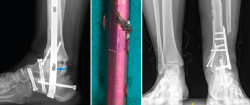

Figura 3. Imágenes del clavo tibiotalocalcáneo roto a través de la trinchera ósea y maniobra de extracción con guías endomedulares ayudadas por la impactación directa en la muesca realizada en el clavo.

Se reintervino al paciente realizando la extracción del fragmento distal del clavo con el sistema extractor del mismo. Para la extracción del extremo proximal fue necesario, además de la utilización de las guías curvadas, abordar el foco de la pseudoartrosis hasta visualizar el clavo y, con una fresa de alta velocidad, hacer una muesca en el mismo. Mediante la percusión sobre un escoplo apoyado en la muesca realizada en el clavo y con la ayuda de las agujas guía introducidas a través del clavo, se consiguió la extracción del extremo proximal a través de la planta del pie (Figura 3). Se legró la superficie articular tibiotalar y se colocó injerto de cresta ilíaca, fijando la artrodesis con una placa TTC (Palex Medical), aunque la articulación subtalar estuviese artrodesada, para dar mayor solidez al montaje.